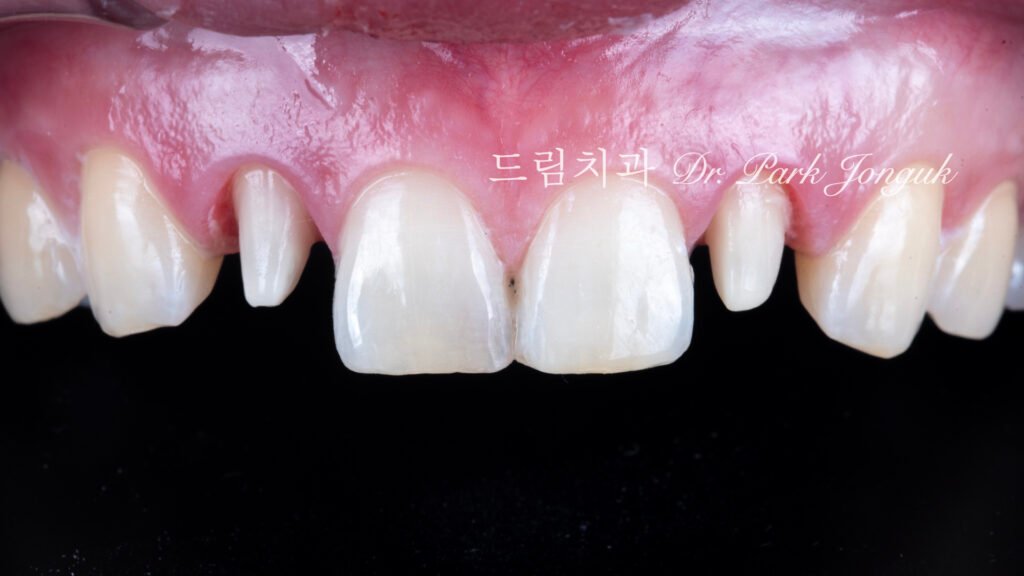

2.1 초진 상태 및 기존 보철물 진단 (사진 1, 2)

[사진 1, 2 참조] 환자분은 말할 때 치아가 거의 노출되지 않는 전형적인 옥니 상태였습니다. 양측 측절치(Lateral Incisor)는 이미 크라운 치료가 되어 있었으나, 주변 자연치와 색상이 어우러지지 않았고 형태적으로도 미흡했습니다.

3. 재시술과 보존의 공존 (사진 7)

3.1 크라운 제거와 삭제에 대한 안타까움 (사진 7)

[사진 7 참조] 기존 올세라믹 크라운을 제거한 후의 모습입니다. 왜소치였음에도 불구하고 과거 시술 시 치아 삭제가 과도하게 이루어져 있는 것을 확인했습니다. 이미 삭제된 치아는 **재시술(Retreatment)**을 통해 보호해야 하며, 나머지 중절치와 견치는 **무삭제(No-prep)**로 진행하여 추가적인 손상을 막기로 결정했습니다.